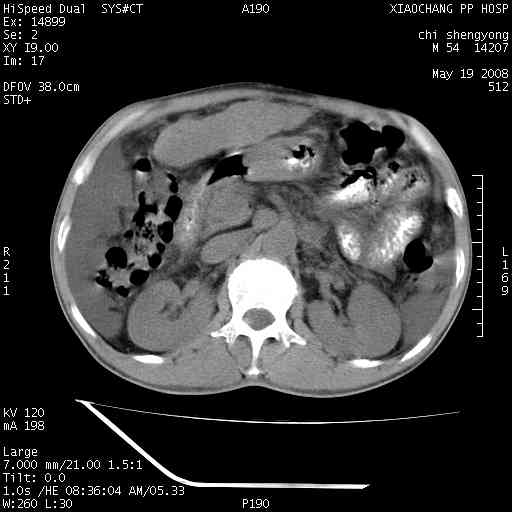

以下是引用zjzjr在2008-5-21 10:52:00的发言:[br]肝左叶巨块型肝癌伴门静脉左支瘤栓形成.肝硬化、腹水,胃底静脉曲张,脾术后改变。

以下是引用随光逐影在2008-5-21 16:20:00的发言:[br]1)肝左叶肝癌伴门静脉左支瘤栓形成,腹膜后淋巴结转移。2)肝硬化、腹水、胃底静脉曲张。3)胆囊炎。4)脾脏缺如,为切除术后所致。